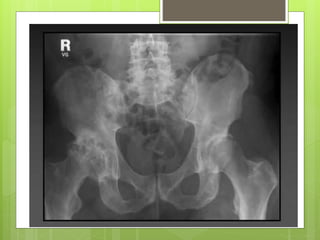

Surgical treatment

Hip:

 Osteotomy – Intertrochanteric osteotomy

 Hip resurfacing

 Total hip replacement.

Surgical treatment Hand  Jointfusion  Joint replacement Knee:  Osteotomy – High tibial osteotomy  Total knee replacement  Arthroscopic debridement Hip:  Osteotomy – Intertrochanteric osteotomy  Hip resurfacing  Total hip replacement.